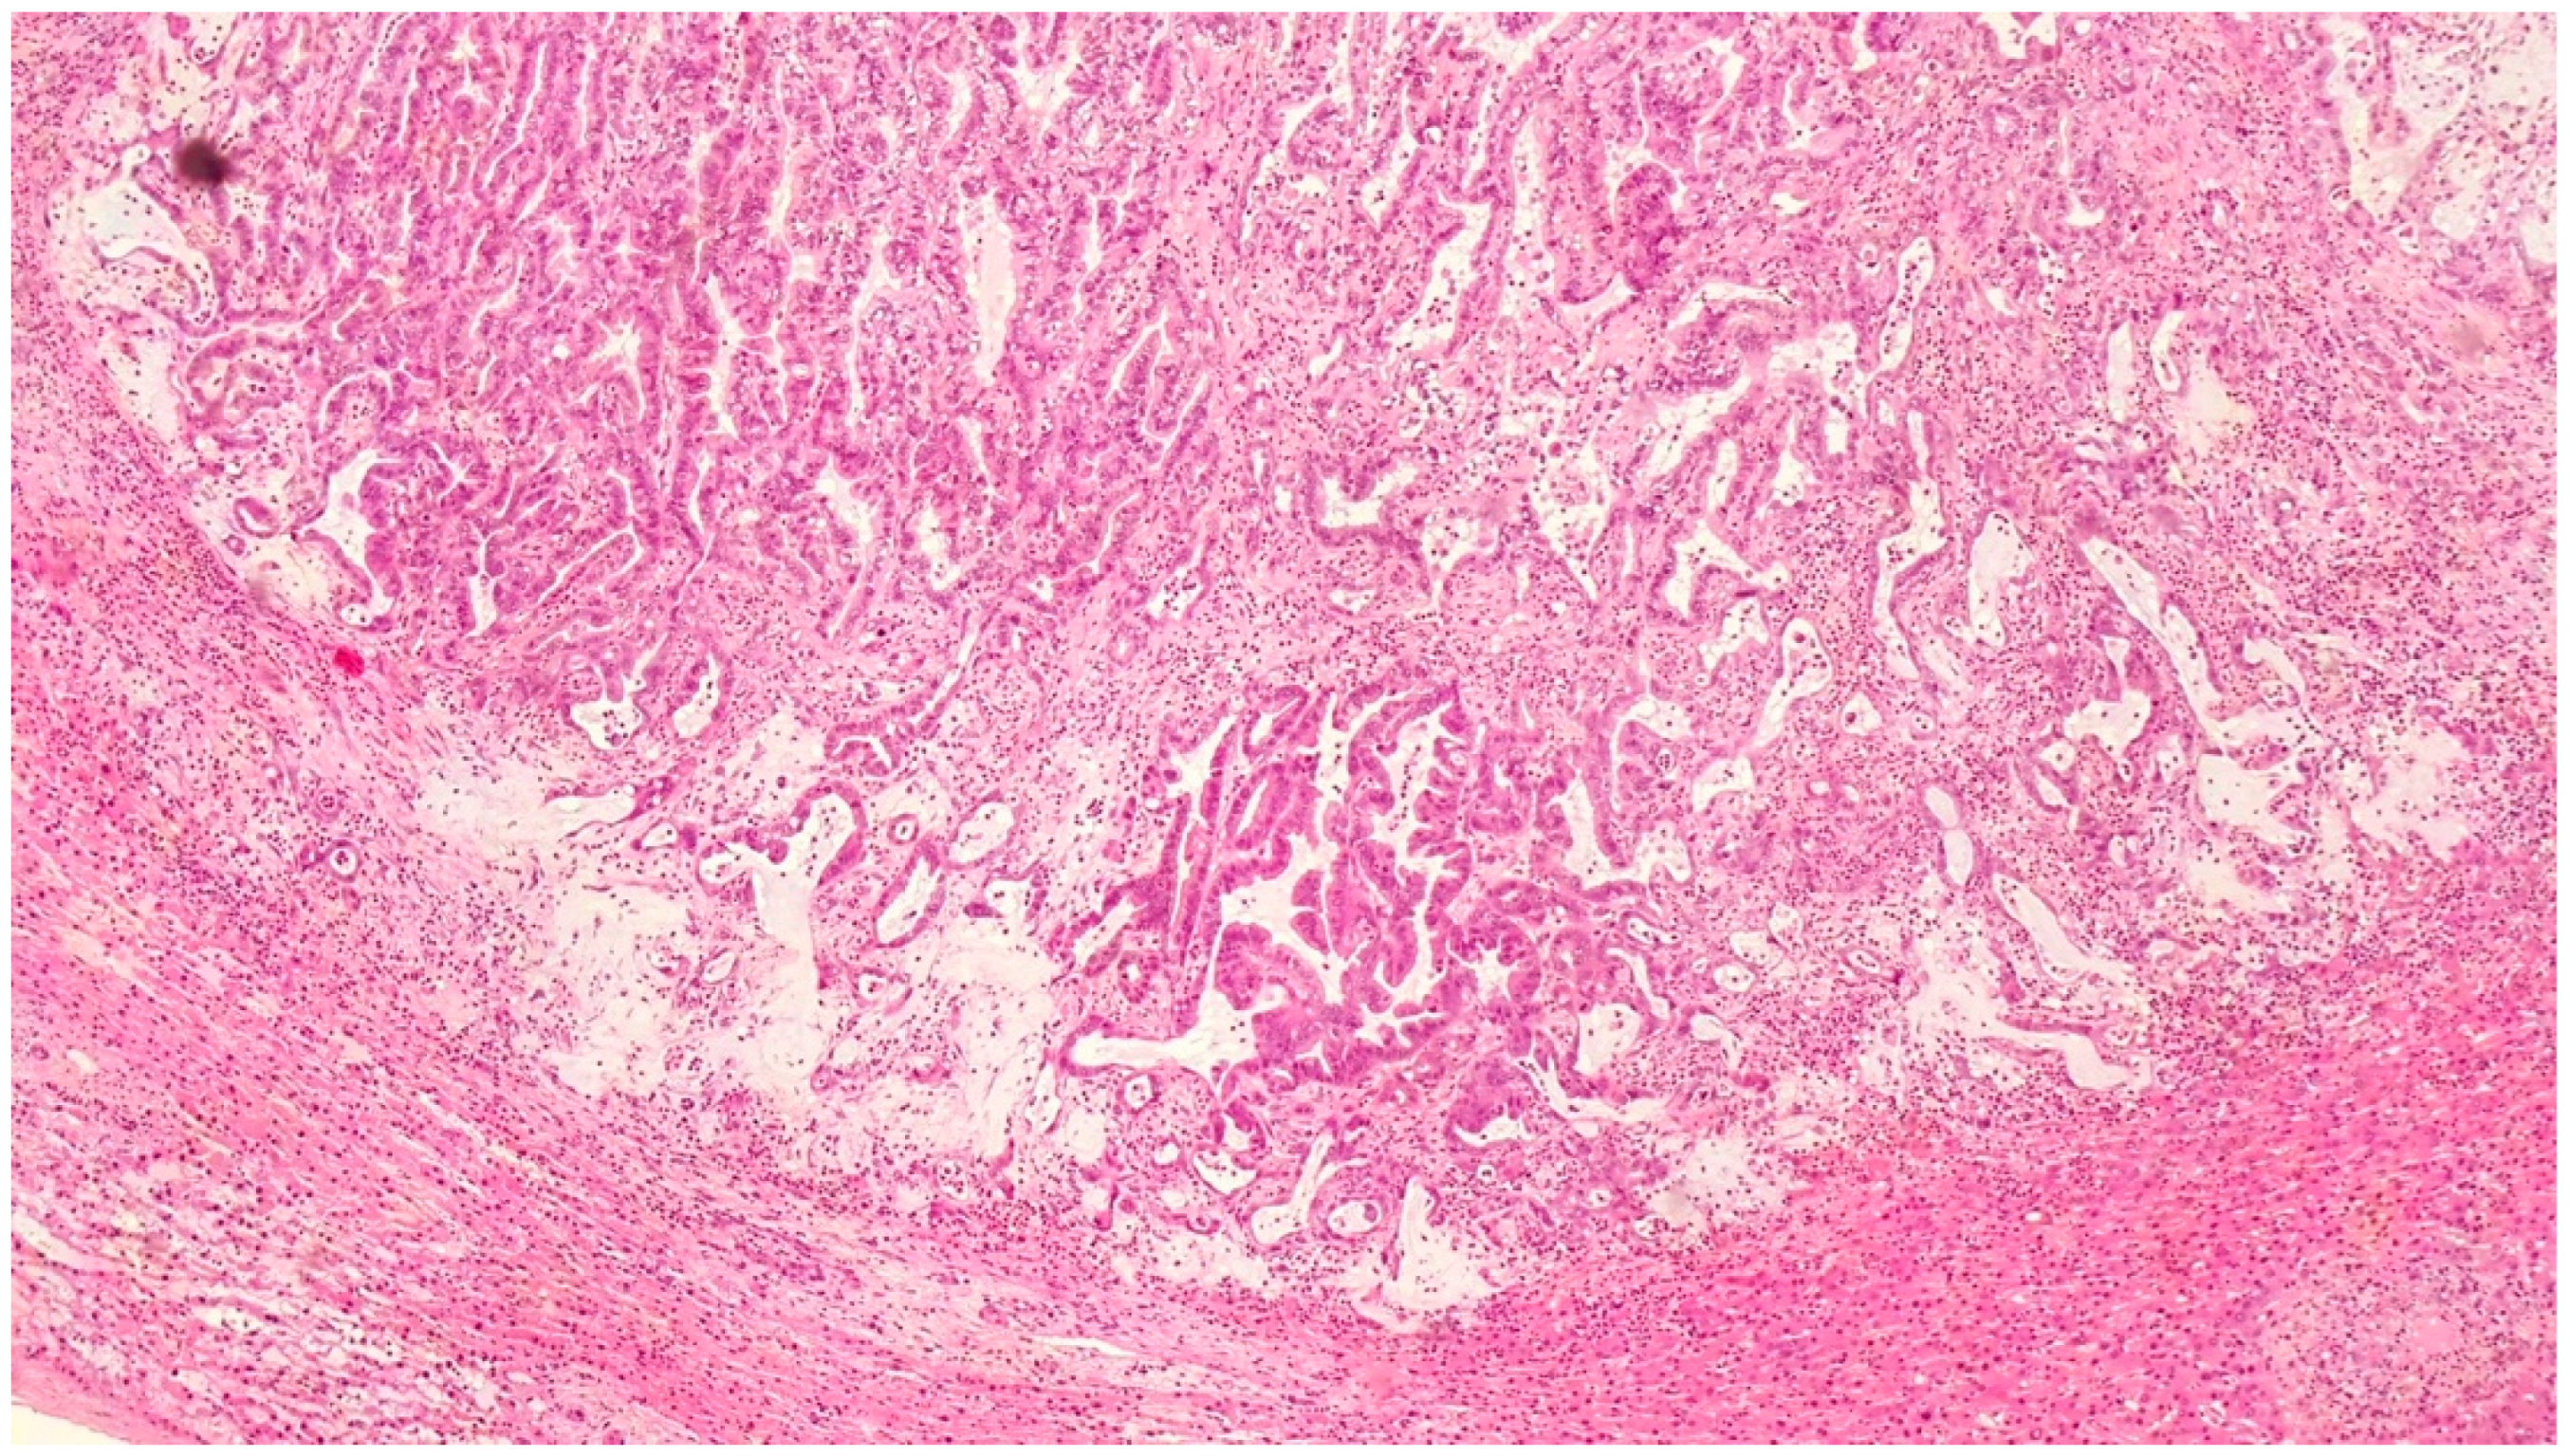

| Histopathological Findings | IPNB with foci of adenocarcinoma, oncocytic appearance, varying degrees of dysplasia, mucus within cyst | Adenocarcinoma with papillary clear cell and mucinous appearance, gland ectasis, cystic or pseudocystic aspects |